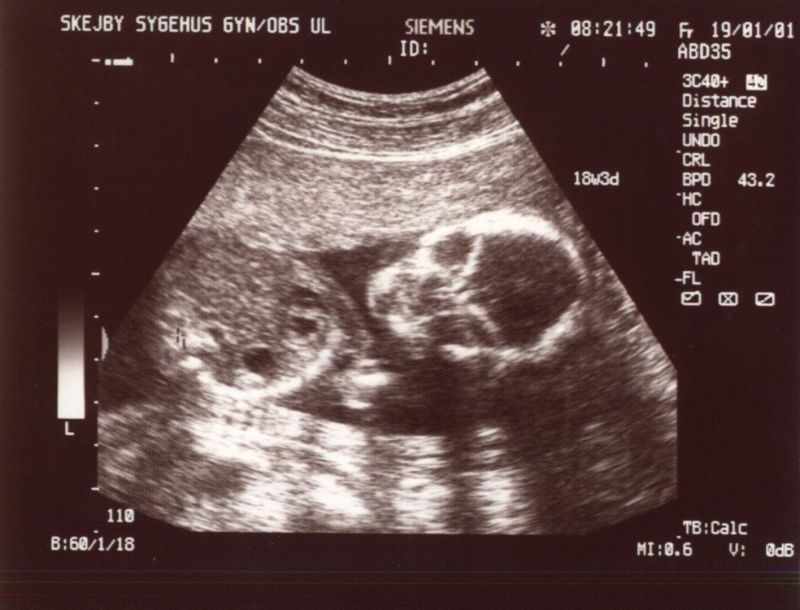

Scannings at the 12th and 19th week of the pregnancy.

Full picture from scanning in the 12th week. Lots of life and movement in there. Same picture, but with explanations. It takes a bit of practice to see anything on these images. Facial shot - looks eerie, but she was looking all the time curiously at the scanner. Really detailed - even though she's 12 cm from head to butt here. Same picture, but with explanations. Sorry, it's all in danish.